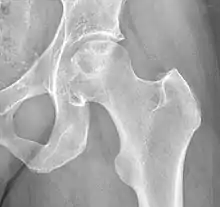

| Other names | Idiopathic avascular osteonecrosis of the femoral head |

| X-ray of hip with femoral head osteonecrosis | |

Chandler's disease, also known as idiopathic avascular osteonecrosis of the femoral head (ANFH or ONFH), is a rare condition in which the bone cells in the head of the femur (FH) die due to lack of blood. This disease is caused when blood flow is reduced to the part of a bone near a joint. It is specifically unique because the femoral head is for some reason the only affected part of the body and rarely travels down to the main part of the femur. In 1948, F. A. Chandler did a multi-case review and first released his interpretations as Coronary Disease of the Hip. This term is now considered incorrect as it improperly describes the actual disease.[1]